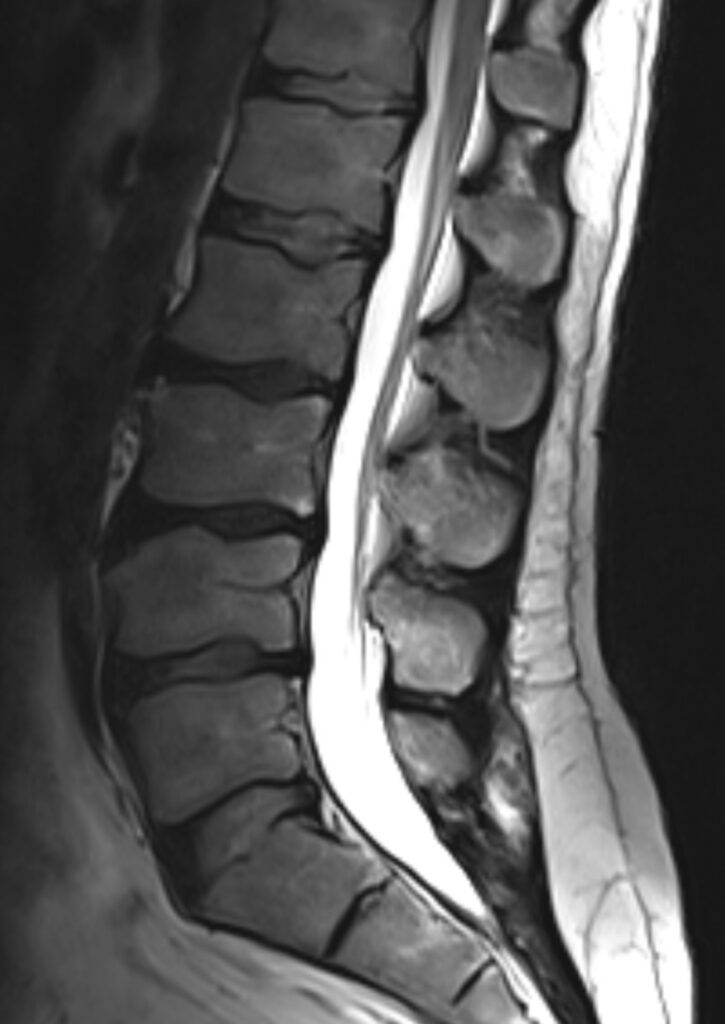

- Lendenwirbelsäule (LWS)

Bei einer Wirbelsäule MRT können sowohl knöcherne Strukturen als auch Weichteile erkannt und folglich untersucht werden. Dadurch eignet sich die MRT Wirbelsäule besonders gut, um Schmerzen mit unklarer Ursache im Rücken und der Wirbelsäule abzuklären. Denn auf den MRT-Bildern des Rückens können Schäden an der Wirbelsäule, den Bandscheiben und am Rückenmark erfasst werden.

Mögliche Erkrankungen an diesen Strukturen sind mit der nicht-invasiven bildgebenden Methode, wie es die Kernspintomographie bzw. Magnetresonanztomographie ist, bereits in frühen Stadien erkennbar, was für viele Patienten die Aussichten auf eine erfolgreiche Therapie erhöht bzw. die Prognose verbessert.

- Bandscheibenvorfall